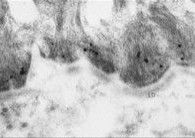

免疫電鏡

免疫電子顯微鏡並不能廣泛使用,用金標記法已證明體內IgG抗體沉積主要在半橋粒下基底細胞膜的外側,與BP180胞外域的定位是一致的。通過間接免疫電鏡,發現針對BP230和BP180的自身抗體分別結合在半橋粒斑(圖8)和半橋粒下透明板水平。